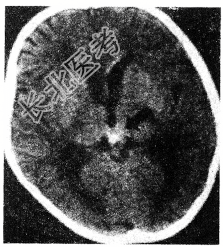

- 单项选择题关于松果体区生殖细胞瘤(如图所示)临床表现叙述不正确的是

A、性发育迟缓

B、尿崩症

C、Parinaud综合征

D、听力障碍

E、共济失调